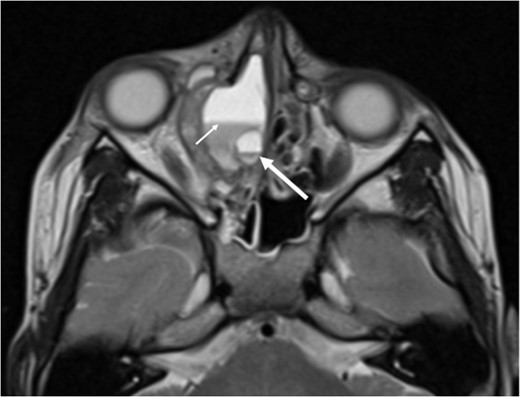

A 6-year-old boy with a background of asthma presented to a tertiary paediatric unit in May 2016 with a 3-day history of right eye pain, proptosis and erythema under the care of the ENT team. A provisional diagnosis of a periorbital cellulitis was made secondary to ethmoid sinusitis and management with intravenous antibiotics (ceftriaxone), intranasal steroids, saline douches and topical oxyxlometazoline was initiated. Ophthalmological assessment demonstrated normal colour vision, acuity and light reflexes bilaterally but also proptosis-related ophthalmoplegia. Computed tomography (CT) imaging of the orbits and paranasal sinuses demonstrated complete opacification of the right-sided paranasal sinuses and compromise of the right frontal and ostiomeatal unit. In addition there was an expansile abnormality centred on the ethmoidal labyrinth with bony remodelling of the lamina papyracea and a subperiosteal collection adjacent to the medial orbital wall (Figs 1 and 2). The most likely diagnosis was felt to be an infective process with mucopyocele formation complicated by a subperisoteal post-septal collection. An MRI scan with gadolinium of the orbits and sinuses confirmed the unilateral pattern of sinus opacification within the right frontal, ethmoids and maxillary sinus. The lesion demonstrated multiple fluid–fluid levels and peripheral enhancement (Figs 3 and 4). The patient was treated by endoscopic drainage of the lesion, which revealed only blood. He initially had some improvement of his proptosis but recurred within a few days and so further, more extensive endoscopic debridement was performed.

Axial T1 post-contrast sequence with fat suppression demonstrating peripheral enhancement (white arrows) but no internal or solid enhancing components to suggest that this is a secondary ABC.

At this point the MRI was reviewed and the possibility of an ABC was raised. This was due to the presence of fluid–fluid levels, cyst within a cyst appearance and lack of restricted diffusion within the sinonasal contents and material drained at the time of the first endoscopic procedure. He was discharged home on oral co-amoxiclav, and topical betamethasone nose drops.